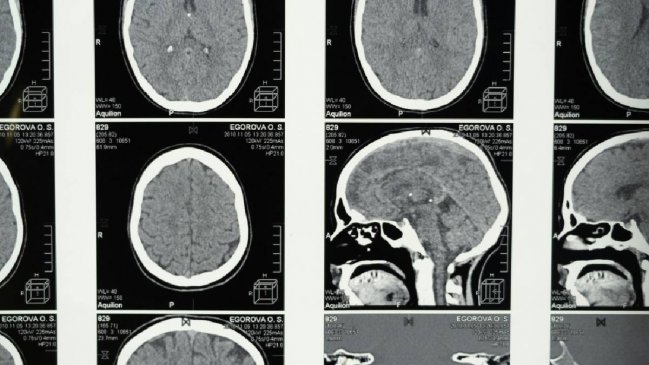

La menopausia está relacionada con la pérdida de materia gris y unos cambios en el cerebro que son similares a los observados en el Alzheimer, según sugiere este martes una investigación de la Universidad de Cambridge.

Así, observaron que la menopausia está relacionada con la pérdida de materia gris, vital para las funciones mentales, la memoria, las emociones y el movimiento, y que también puede provocar ansiedad, depresión y problemas de sueño.

Las mujeres respondieron preguntas sobre temas como el sueño y si sufrían de depresión y ansiedad, mientras que algunas participaron en pruebas cognitivas. Alrededor de 11.000 mujeres también se sometieron a resonancias magnéticas (RM) para que los investigadores pudieran observar la estructura del cerebro.